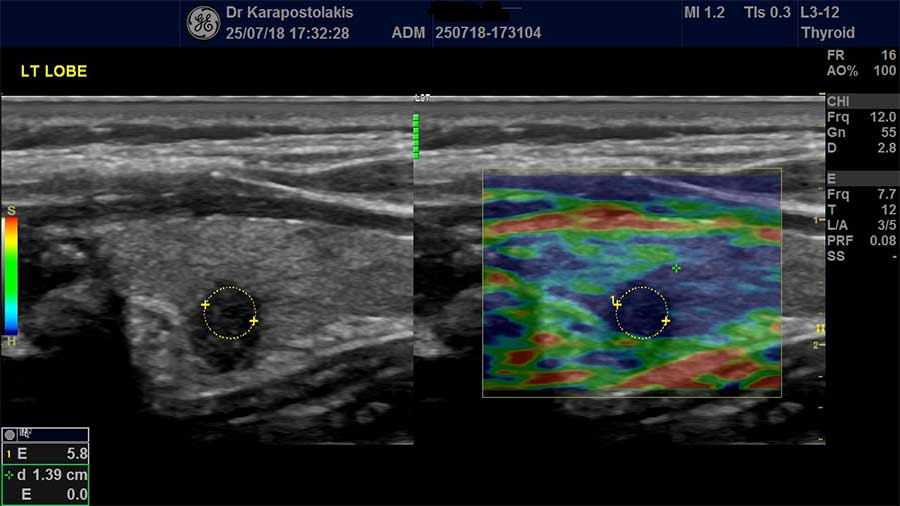

Στο Ιατρείο Υπερήχων Παιδιών & Ενηλίκων χρησιμοποιείται η Ελαστογραφία (SE) στη μελέτη:

- όζων θυρεοειδούς,

- λεμφαδένων,

- όγκων ή μορφωμάτων σιελογόνων αδένων (παρωτίδα, υπογνάθιος αδένας),

- μορφώματα στο μαστό,

- επιφανειακές βλάβες στον υποδόριο ιστό.

Γενικά η Ελαστογραφία χρησιμοποιείται ως συμπληρωματικό «εργαλείο» στον υπερηχογραφικό έλεγχο όλο και περισσότερο τα τελευταία χρόνια. Η ειδικότητα της μεθόδου εξαρτάται από την εμπειρία του εξεταστή.

Στο Ιατρείο Υπερήχων Παιδιών & Ενηλίκων λόγω της συνεργασίας με διεθνούς φήμης και κύρους κυτταρολόγο έχουμε τη δυνατότητα να ταυτοποιούμε σχεδόν καθημερινά τα αποτελέσματα της ελαστογραφικής μελέτης με το κυτταρολογικό έλεγχο σε περιστατικά όπου πραγματοποιείται FNA. Η εμπειρία αυτή μας επιτρέπει να βελτιώνουμε συνεχώς τη μεθοδολογία μας αυξάνοντας παράλληλα την ευαισθησία και την ειδικότητα της Ελαστογραφίας.